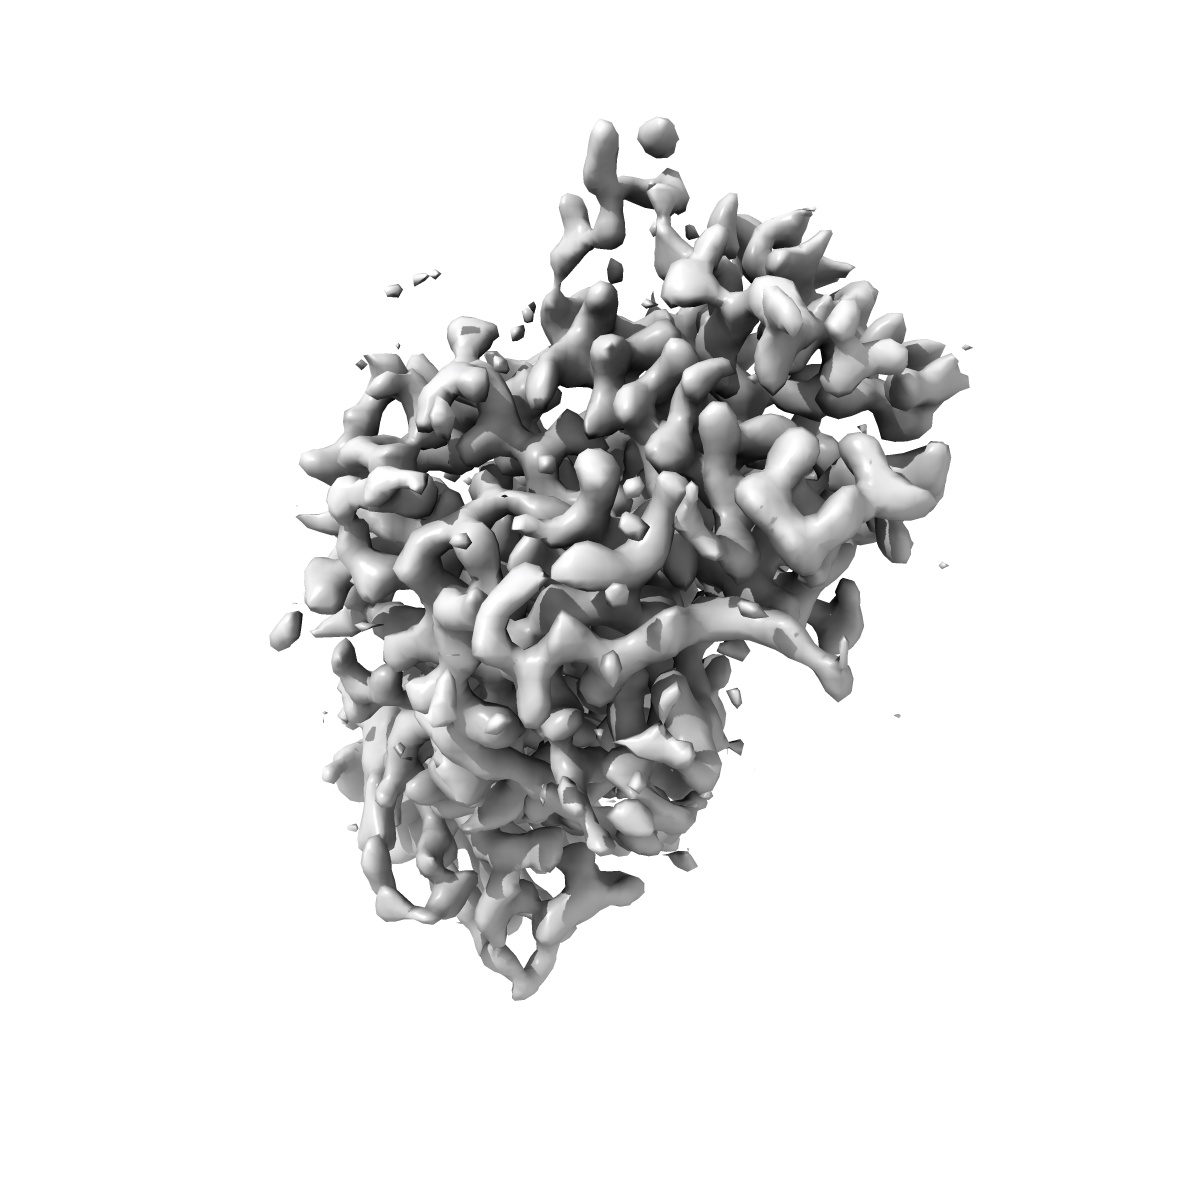

EMD-48537

A8 Fab in complex with CD97

Single-particle

3.16 Å

Sample Organism: Homo sapiens

Sample: A8 Fab in complex with CD97

Fitted models: 9mqr

Deposition Authors: Hattori T , Bang I, Fang M, Koide S

Engineering antibody-drug conjugates targeting an adhesion GPCR, CD97.